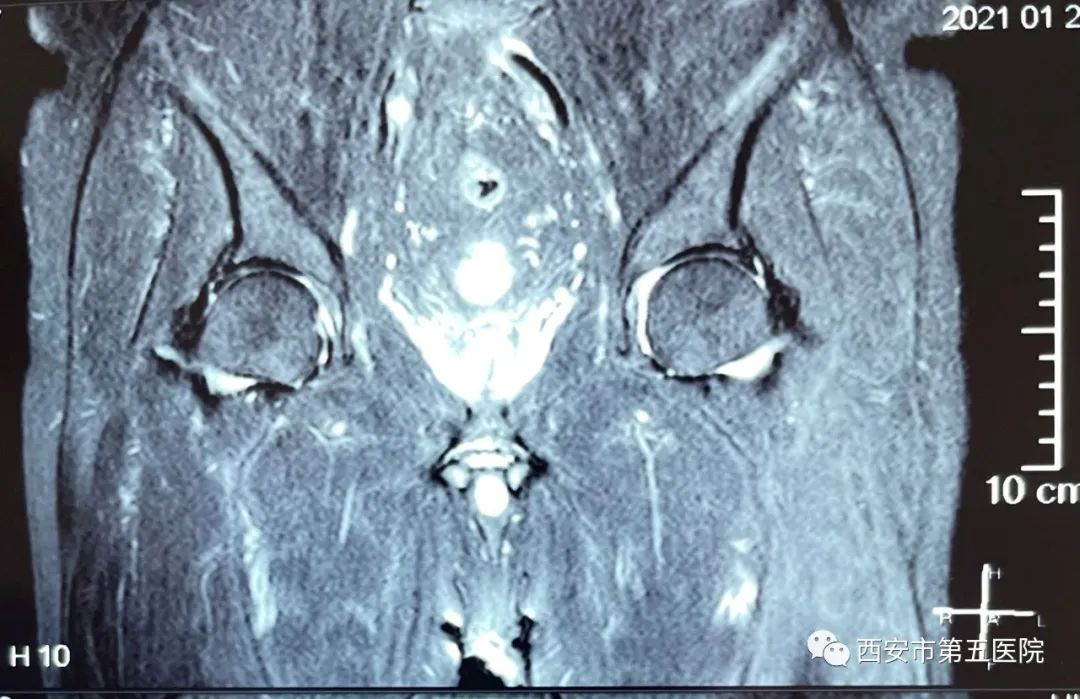

图1核磁共振提示双侧髋关节积液

经过骨科贺强副主任带领骨科一病区全体医生团队的仔细问诊和检查,诊断:双侧髋关节滑膜炎。对患者具体情况进行周密研判分析讨论,确定了两种治疗方案,一种方法是严格卧床、药物治疗,但恢复时间很长,患者难以耐受,身心俱疲的他将会雪上加霜;另一种方案是行髋关节穿刺术,即抽出髋关节腔积液后再行关节腔封闭,优势是患者恢复快,疼痛缓解立竿见影。与患者充分沟通,耐心讲解两种方案利弊,征得患者同意后,决定行髋关节穿刺术。